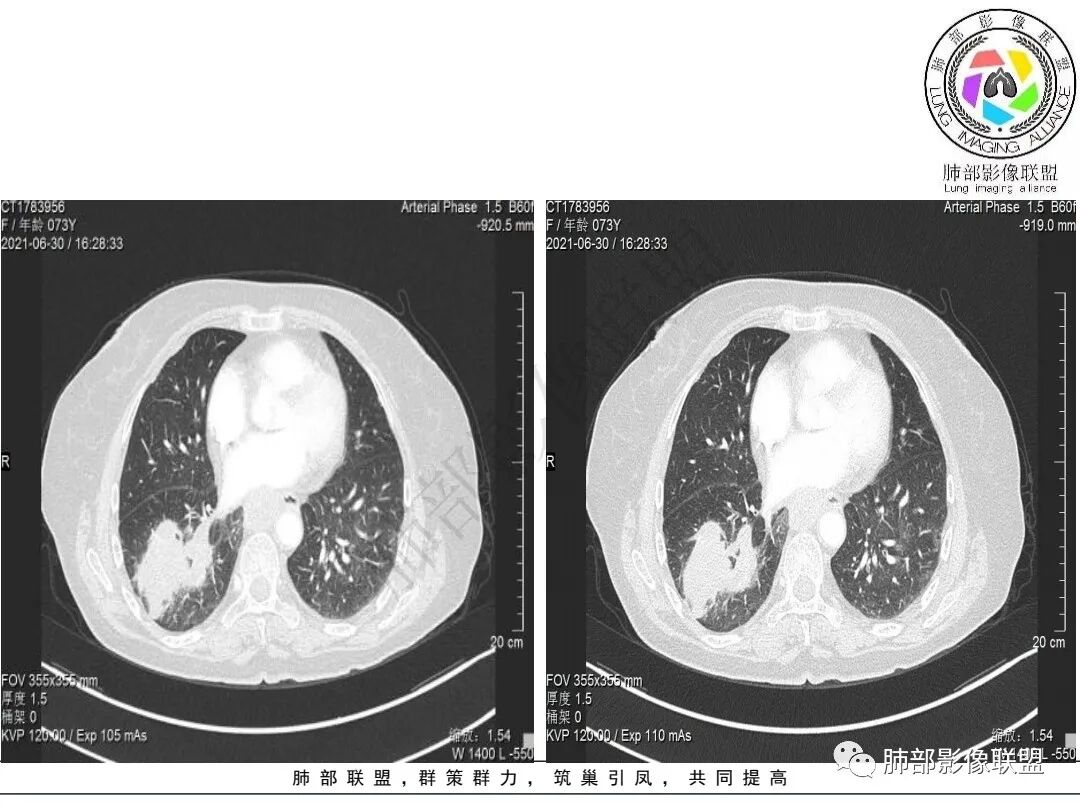

2.右肺下叶不规则实性密度块影,占据外后基底段及背段较大范围,可见轻度分叶、毛刺及棘状突起,未见明显胸膜牵拉及凹陷。

3.右肺下叶支气管轻度狭窄,病灶内见部分充气支气管征,外后基底段不能连续跟踪。

轻度不均匀强化,病灶内小血管显示不满意,未见明确坏死区。

4.右肺门及纵隔见多处增大淋巴结,不均匀环形强化,后下纵隔(隆突下)肿大淋巴结十分显眼!

1)女性不吸烟患者,病灶虽强化不显著,但未见大范围坏死或空洞,肺鳞癌的可能性较小。

2)块影收缩乏力,强化不显著,不是典型的肺腺癌影像学表现。

3)病灶强化不显著,支气管相关,纵隔淋巴结肿大明显,小细胞癌的可能性是比较大的。黄勇老师曾统计后下纵隔(隆突下)显著肿大淋巴结,小细胞癌占比相当高,临床实践也是如此。

4)应当排除的还有粘液表皮样癌、腺样囊性癌、淋巴上皮瘤样爱、混合癌等等……